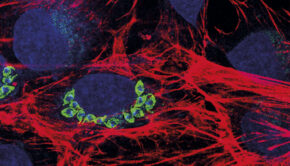

Imagem mostra ninhos do parasita Trypanosoma cruzi em células cardíacas

Câncer é um termo guarda-chuva usado para agrupar mais de 100 doenças, todas caracterizadas pelo crescimento descontrolado de células. Fruto... Ver artigo